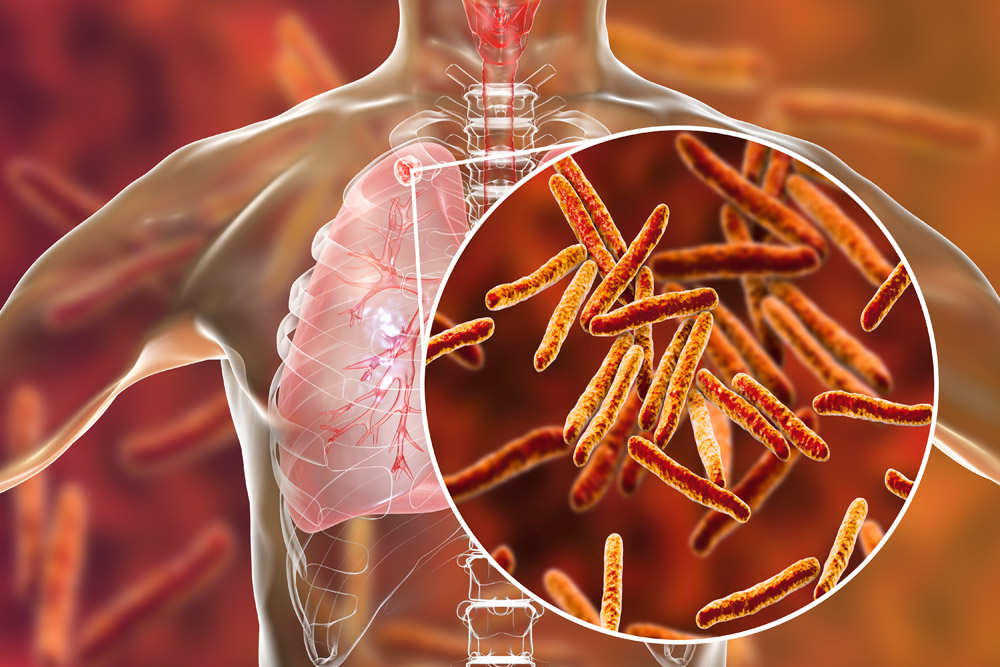

The Tuberculosis Preventive Treatment (TPT) Training Program is a collaborative initiative led by esteemed organizations such as the World Health Organization (WHO), the Global Fund, and the Tuberculosis Control Programme of Ghana, operating under the auspices of the Ghana Health Service and the Ministry of Health. This program strategically focuses on enhancing Tuberculosis Preventive Treatment for People Living with HIV (PLHIV) and Contacts of TB Patients in Ghana.

Distinguished as a ground-breaking initiative, this program remains a pivotal component of the broader Strategic Initiative (SI) on TB preventive treatment. Employing a sophisticated e-learning methodology, the training is intricately designed to deliver a comprehensive and adaptable learning experience for healthcare professionals. This approach is tailored to accommodate the diverse schedules and preferences of participants, fostering a self-paced learning environment that ensures optimal engagement and knowledge retention.